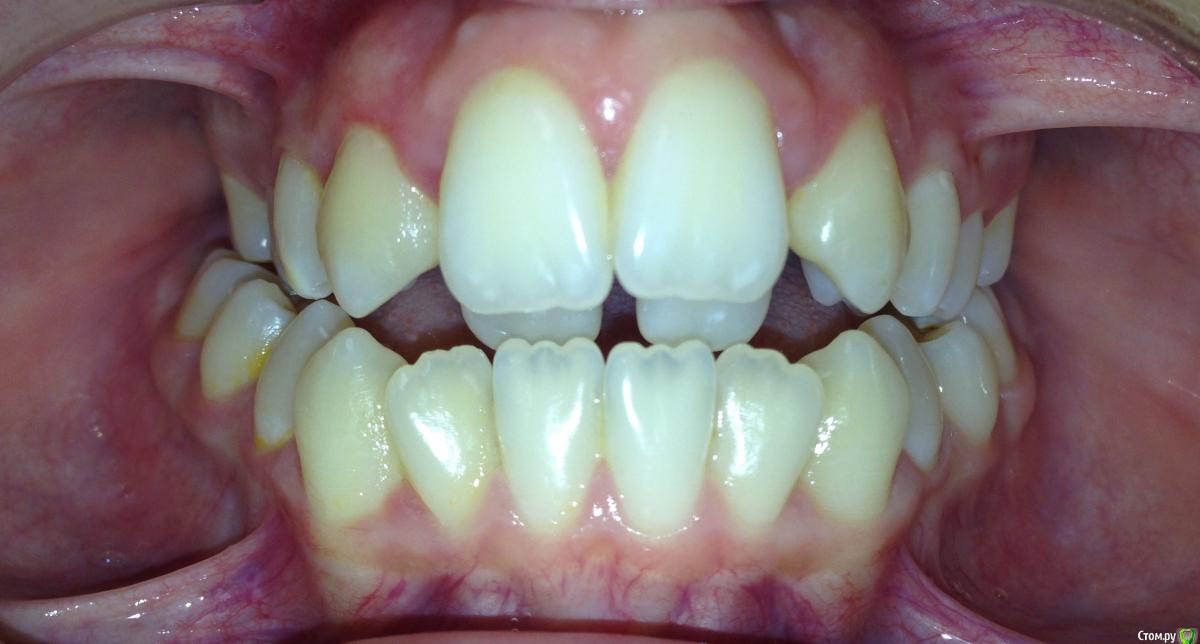

Алевтина Петровна Опубликовано 26 августа, 2015 Поделиться Опубликовано 26 августа, 2015 Всем добрый вечер. Я начинающий ортодонт. Надеюсь,что вы поможете с планом лечения. Пришел пациент. 13 лет. Ситуация по мне непростая, но очень интересная. Ссылка на комментарий

Алевтина Петровна Опубликовано 26 августа, 2015 Автор Поделиться Опубликовано 26 августа, 2015 Прикрепляю дополнительные фото, извините за качество. Это моя первая публикация, пытаюсь разобраться. Ссылка на комментарий